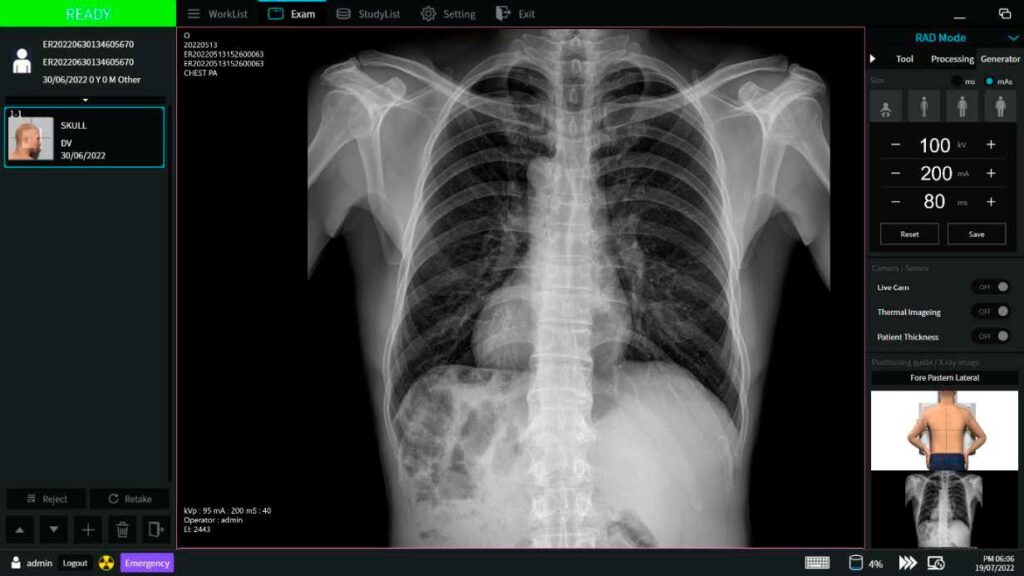

- Radiografía

Interfase Digital

- Guía de posición

Radiografía

- Flujo de trabajo simple

- Examen de emergencia

- Previsualización de imágenes

- Tiempo de procesamiento de imágenes rápido (<0.8 Seg.)

- Procesamiento de imágenes avanzado